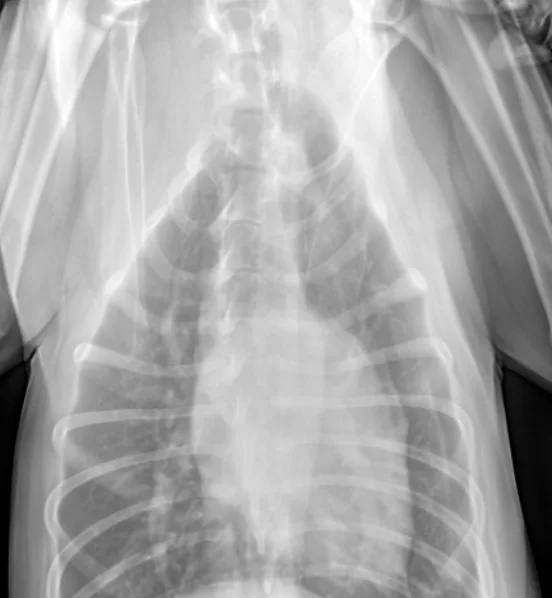

An alveolar pattern in the entire left hemithorax and in the hilar and midzone regions of the right caudal lung lobe. Multiple air bronchograms are observed in the left hemithorax on both views.

Recheck thoracic radiographs obtained 35 hours after admission revealed a progressive alveolar pattern affecting the left cranial, left caudal, and right caudal lung lobes. Consolidation was noted in the left cranial lung lobe (Figure 1, above).